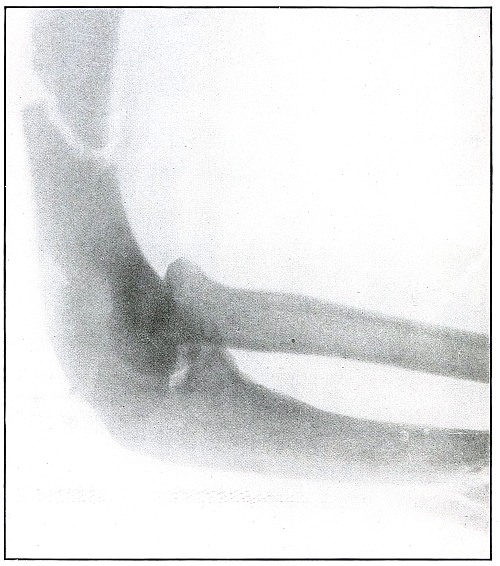

Plate 17.

_

[Pg 45]

Rifle—Plate 17.

UPPER EXTREMITY.

Gunshot Fracture of the Elbow.

The bullet in transverse course and high velocity through both bones of the forearm struck the head of the radius, thus starting several splitting lines of fracture and separating large fragments. Smaller fragments which received some of the energy of the missile have been carried along with it in turn, striking the ulna and carrying away smaller fragments from it and causing the laceration which marks the wound of exit.

Such wounds, with laceration of soft parts and fragmentation of the bone, are prone to infection, against which treatment is directed. The indications to be met are much like those of the wound shown in plates 18 and 19. Excision or immediate methods of bone repair are contraindicated by infection.

Results will depend upon the nature and extent of infection. [Pg 46]